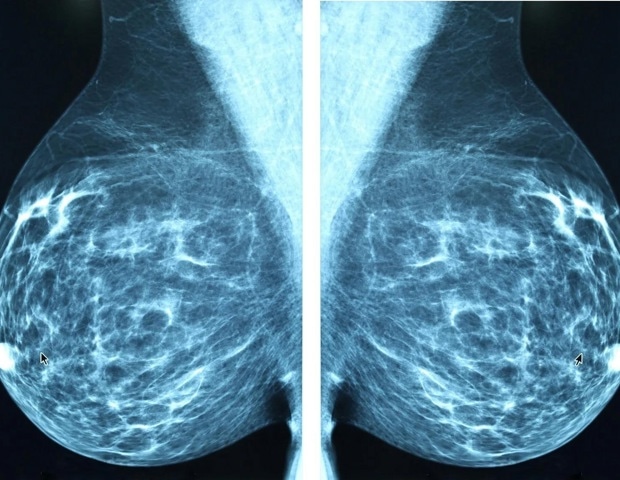

Новое антитело подавляет рост первичной опухоли и распространение тройного негативного рака молочной железы

Тройной негативный рак молочной железы (ТНРМЖ) — одна из наиболее агрессивных и резистентных к лечению форм рака молочной железы. Он быстро растет, рано распространяется и лишен рецепторов гормонов, которые позволяют лечить другие виды рака молочной железы с помощью таргетной терапии. Даже когда пациенты первоначально реагируют на лечение, рак часто возвращается и становится более устойчивым, чем раньше.

Новое исследование, опубликованное в журнале «Breast Cancer Research», указывает на многообещающую стратегию преодоления резистентности рака. Исследователи из Онкологического центра MUSC Hollings разработали антитело, которое блокирует несколько способов выживания, роста и уклонения клеток TNBC от иммунной системы. В ходе ранних испытаний антитело подавляло рост первичной опухоли и распространение рака на легкие, а также активизировало борющиеся с раком иммунные клетки. Он убивал даже раковые клетки, которые перестали реагировать на химиотерапию.